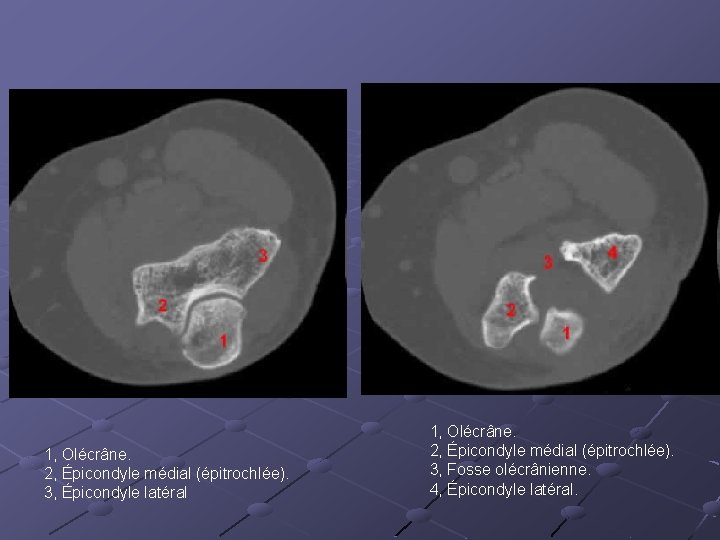

1, Olécrâne. 2, Épicondyle médial (épitrochlée). 3, Épicondyle latéral 1, Olécrâne. 2, Épicondyle médial (épitrochlée). 3, Fosse olécrânienne. 4, Épicondyle latéral.